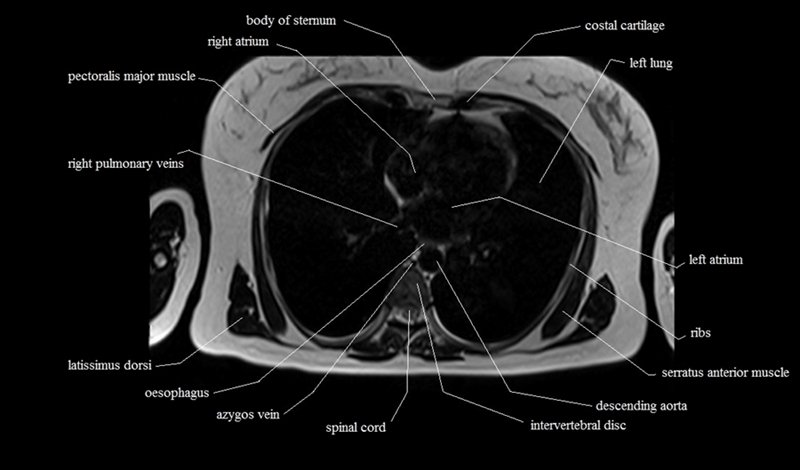

MRI Axial Cross Sectional Anatomy of Chest

This MRI chest (thorax) axial cross sectional anatomy tool is absolutely free to use. Use the mouse scroll wheel to move the images up and down, or alternatively, use the tiny arrows (→) on both sides of the image to navigate through the images. For a more detailed view, double-click the image to view it in full screen, and use the menu in the top right-hand corner to view individual slides or play them in a loop.